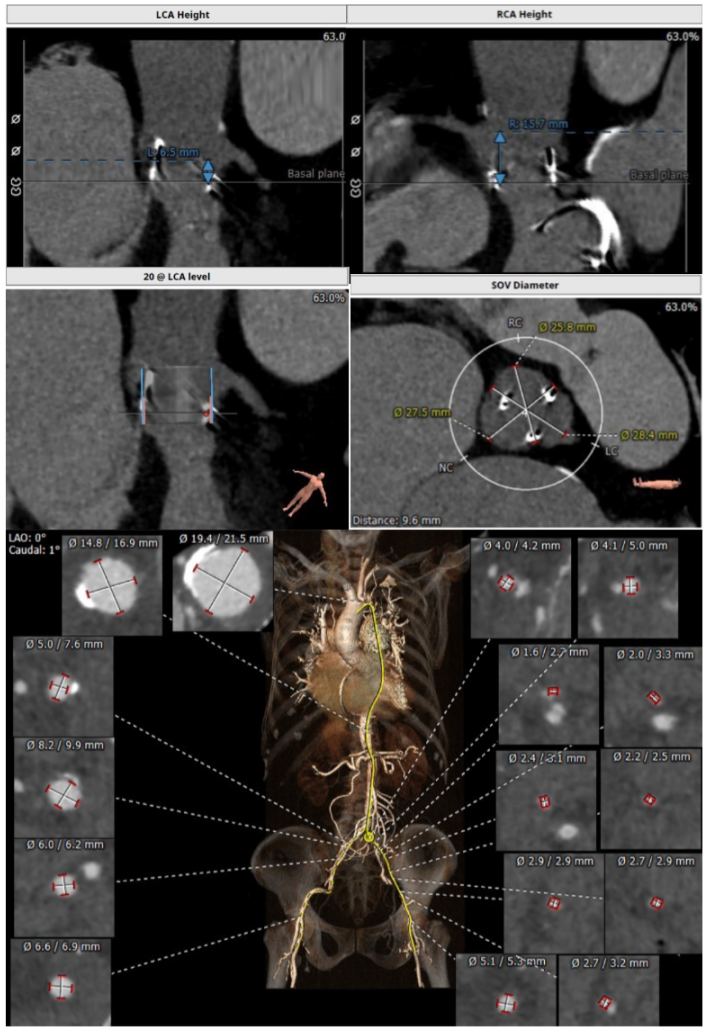

主瓣瓣中瓣CT评估